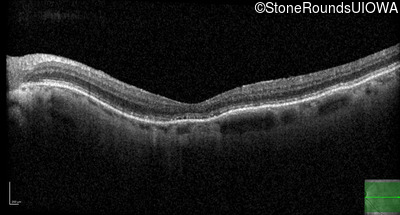

The clinical features favoring the diagnosis of RP1L1-associated occult macular dystrophy include: reduced acuity with a near-normal ophthalmoscopic appearance, a history of normal acuity in childhood; and, a "moth-eaten" appearance of the macular ellipsoid zone on OCT.

Age at visit: 79 years